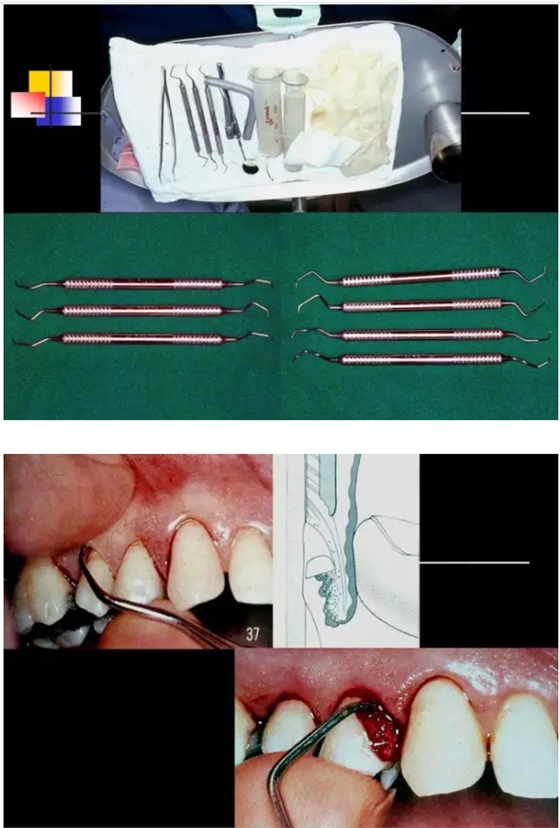

【牙科知識(shí)】牙周病相關(guān)手術(shù)圖解,非醫(yī)學(xué)專業(yè)勿點(diǎn)